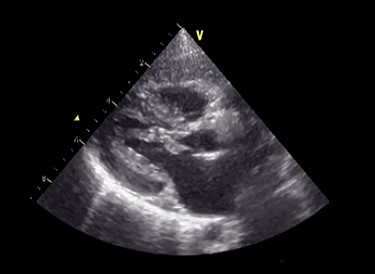

Preoperative echocardiography. The abnormal muscle band in left ventricle and severe SAM of the mitral valve are observed. The anterior leaflet of mitral valve obstructs the LVOT in the systolic phase.

A male infant born at 34-week gestation with 1531-g birth weight was diagnosed with porencephaly based on fetal examination. The patient had persistent hemolytic anemia and jaundice and was diagnosed with a mutation in collagen type IV alpha 1 chain (COL4A1) by postnatal genetic analysis. The details of metabolic and muscular complications of the patient were described in a previous report [2]. The patient underwent surgery for ventriculoperitoneal shunt placement for hydrocephalus and seizure at the age of 3 months and was hospitalized several times for recurrent pneumonia until the age of 2 years, at which time he was diagnosed with LVOTS and moderate MR. The patient was treated with β-blockers for 6 months, but LVOTS and MR gradually worsened and SAM of mitral valve was detected at the age of 2 years and 8 months. At the time, the peak pressure gradient of left ventricular outflow tract (LVOT) was 120 mmHg and the MR was severe (Fig. 1 and Video 1). Surgery was planned for septal myectomy for LVOT with mitral valve repair.